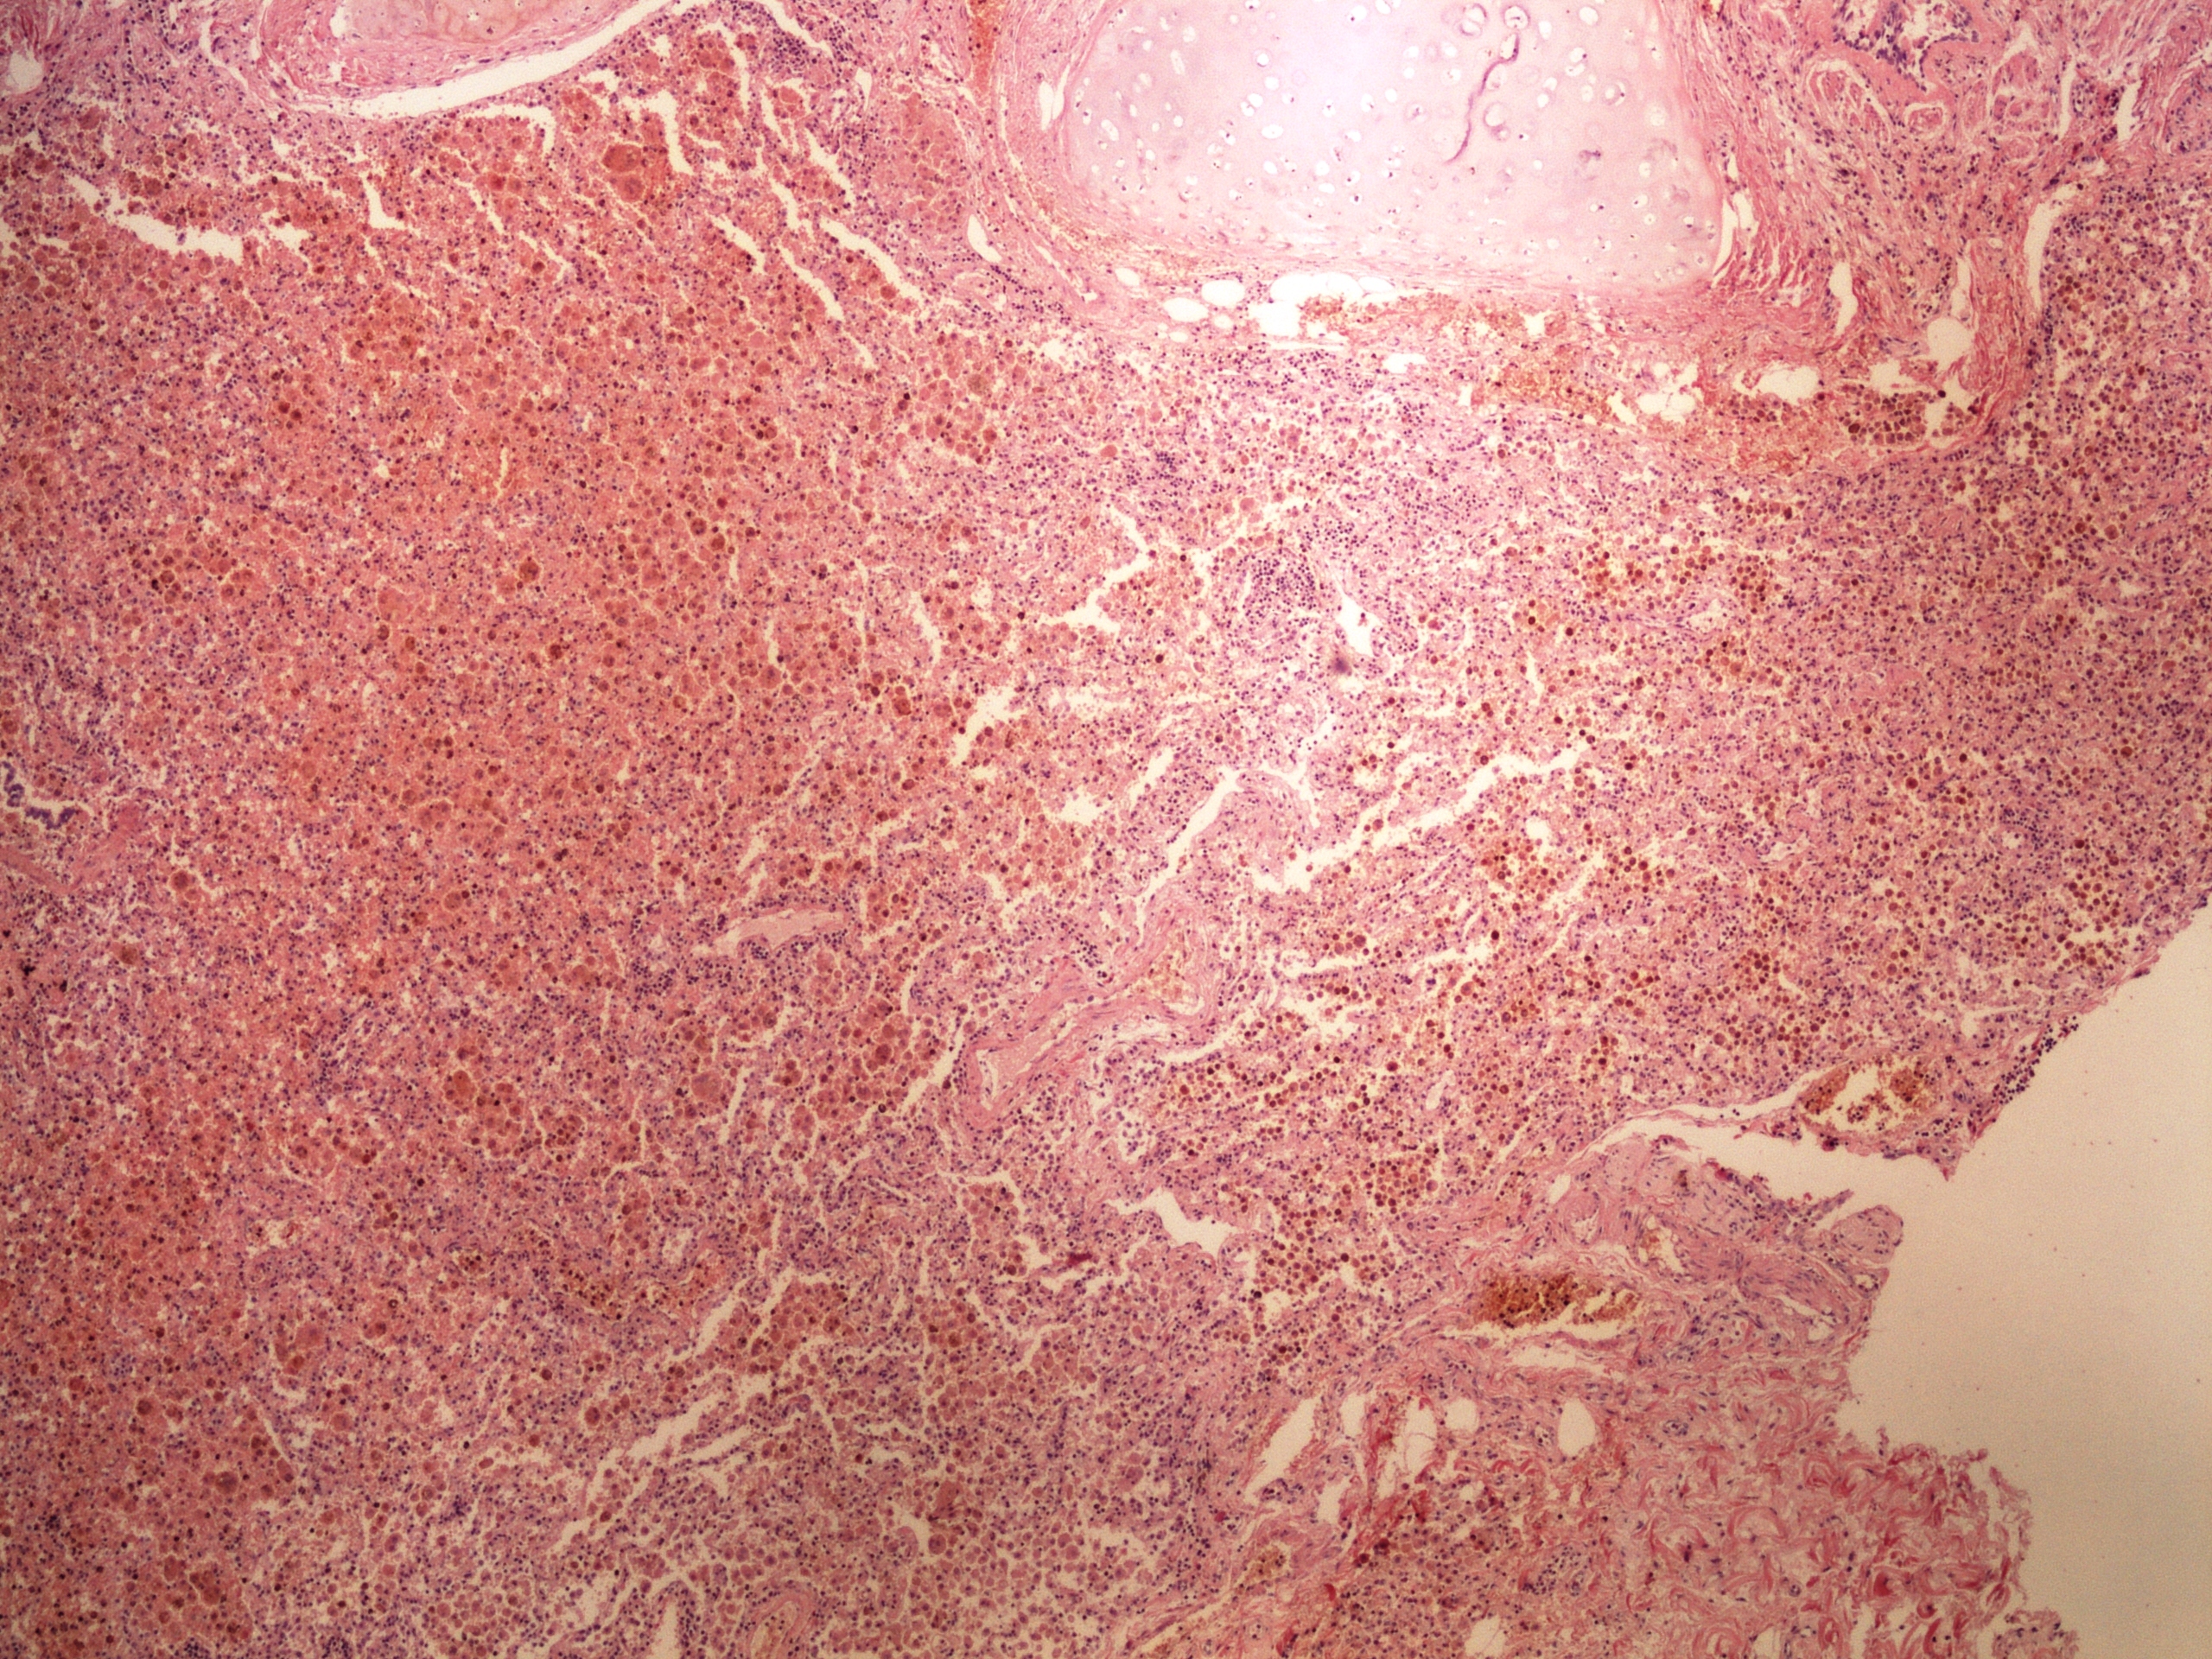

Preparát č.7 a č.8 - antrakóza

Struktury

- makrofágy

- alveoly